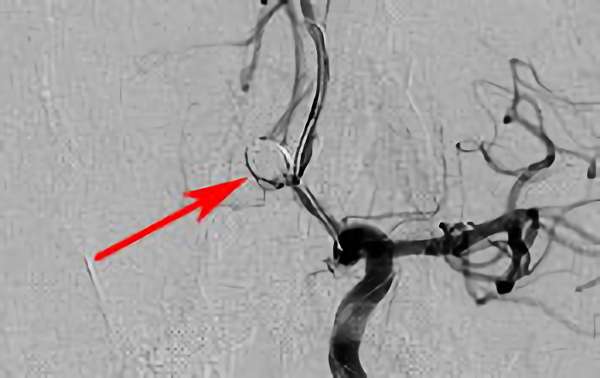

左椎骨動脈後下小脳動脈分岐部動脈瘤

70代

院内外来

No.1628 手術中